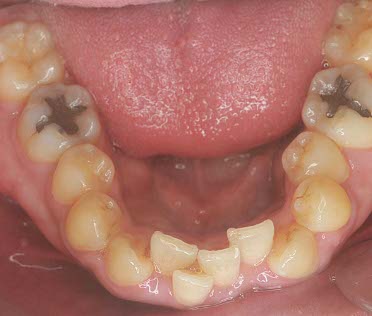

初診相談後、治療をご希望される場合は、初診検査を実施します。この検査で、患者様の現在の口腔内の状態を確認します。

顔貌・口腔内写真の撮影

レントゲン撮影

歯型の模型採取